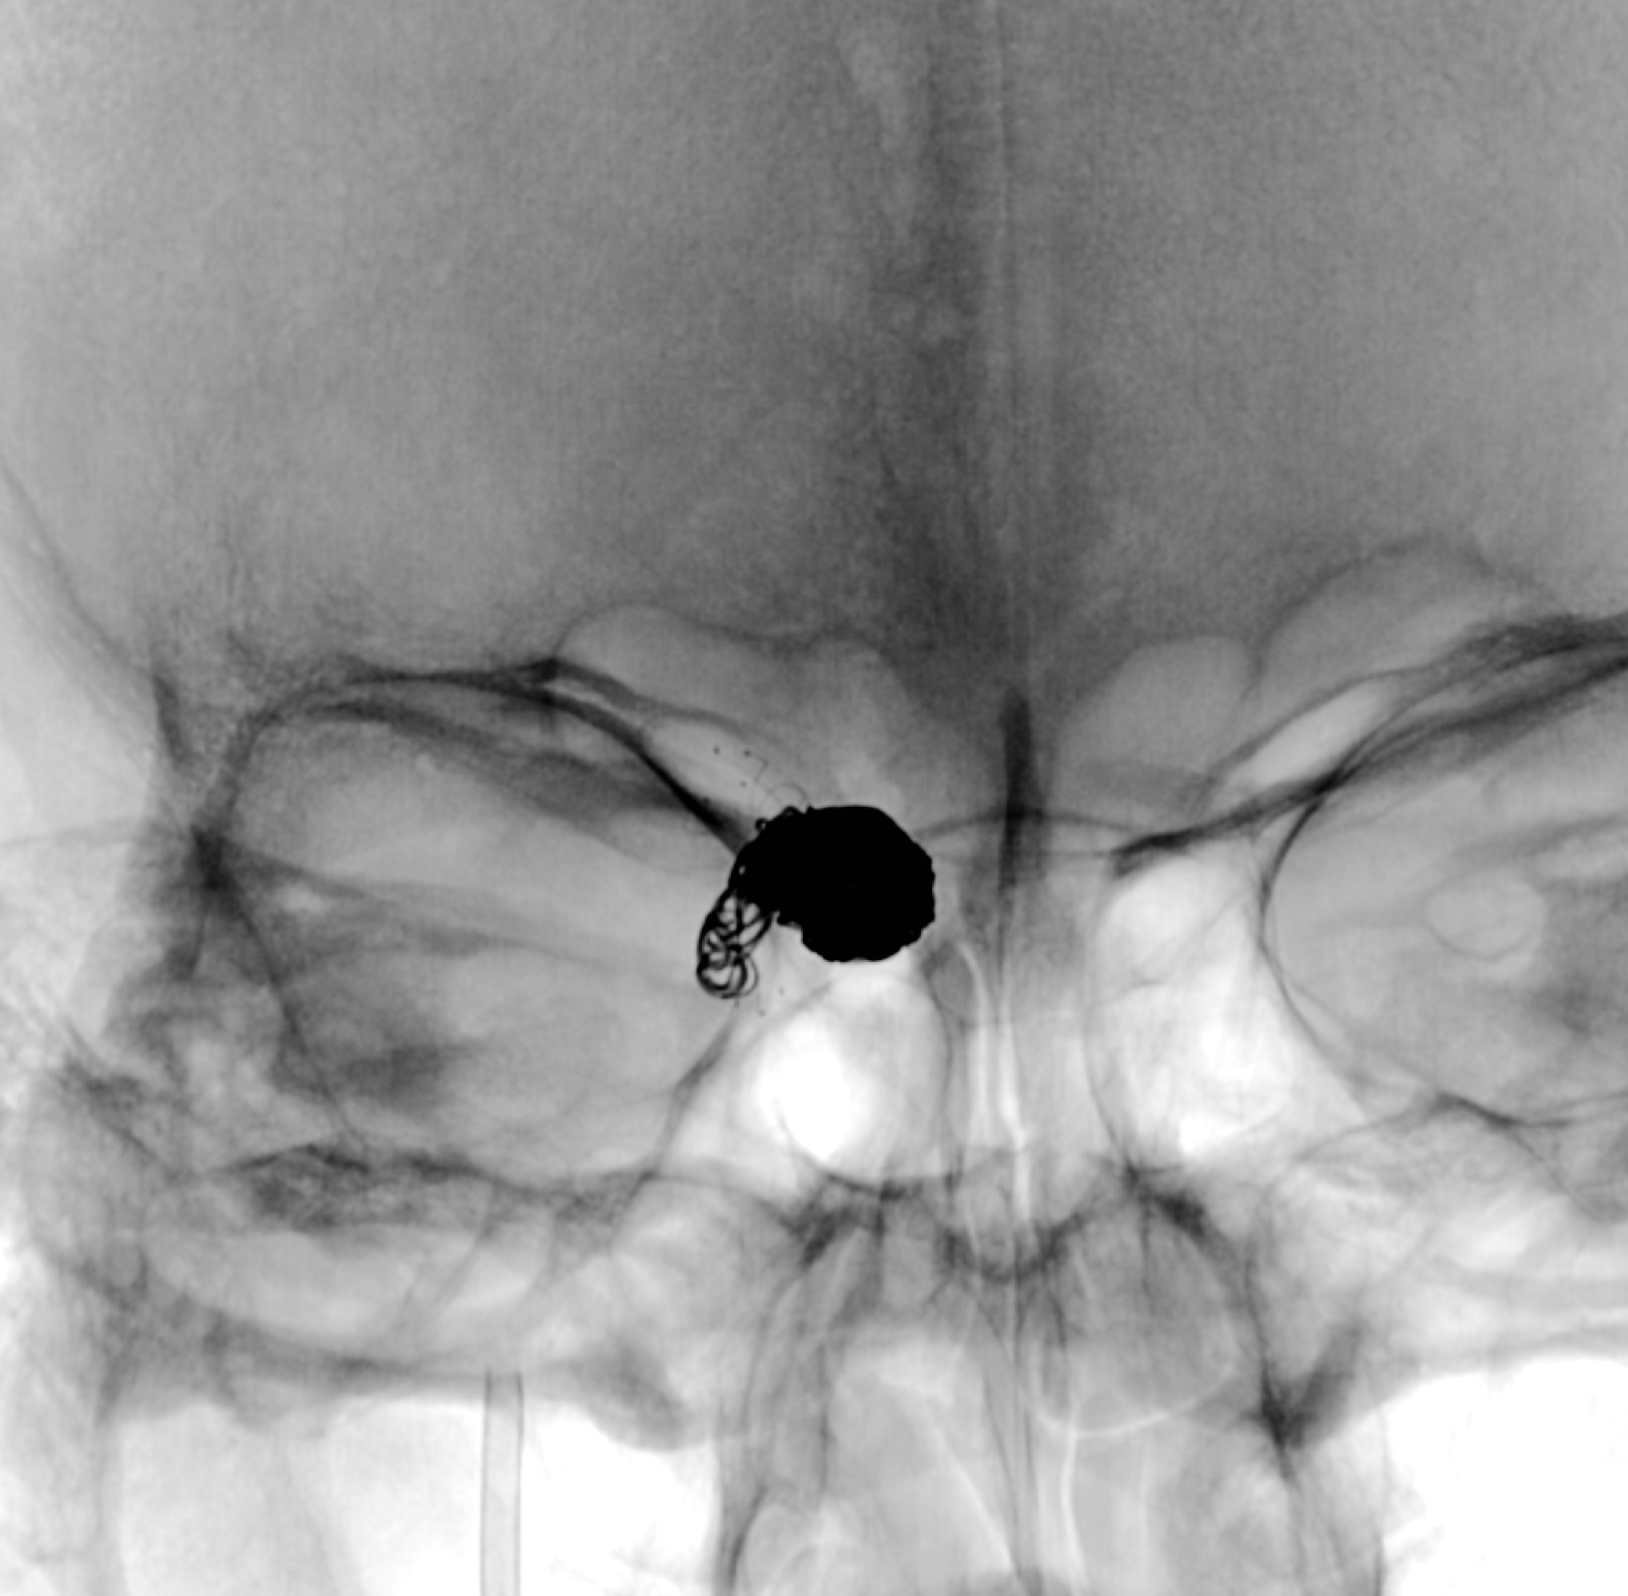

蒙片显示:支架贴壁良好!部分弹簧圈被支架贴附于近端瘤颈及正常颈内动脉内壁!

正侧位蒙片显示:支架及弹簧圈形态良好!